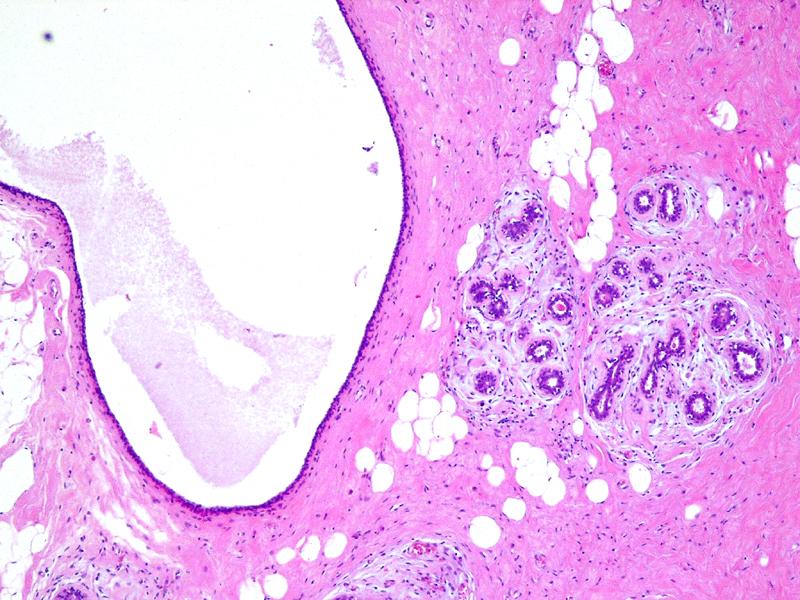

Исследование: микропрепарат молочной железы в медицине

Раздел: Снимки-откровения